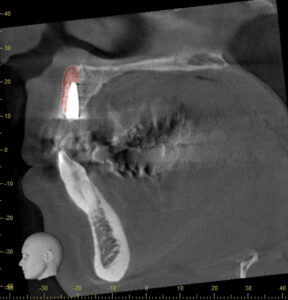

抜歯後、歯茎と骨の治癒を待ちCT画像で骨の状態を確認します。

抜歯した部分を横から見た断面図です。

計測すると骨の厚みは3.5mm程度です。

インプラントのポジションを決まるため、シュミレーションしていきます。

太さ3mmほどのインプラントで理想的な位置に置いてみると、インプラントの一部が骨から露出してしまうことが予想できます。

その場合将来的にインプラントが骨から脱落してしまう可能性が高くなります。

そのため、インプラントするには骨を増やす処置(骨造成、GBR)が必要です。。

今回は一定の骨の厚みはあるため、インプラントと同時に骨造成を行う計画を立てました。